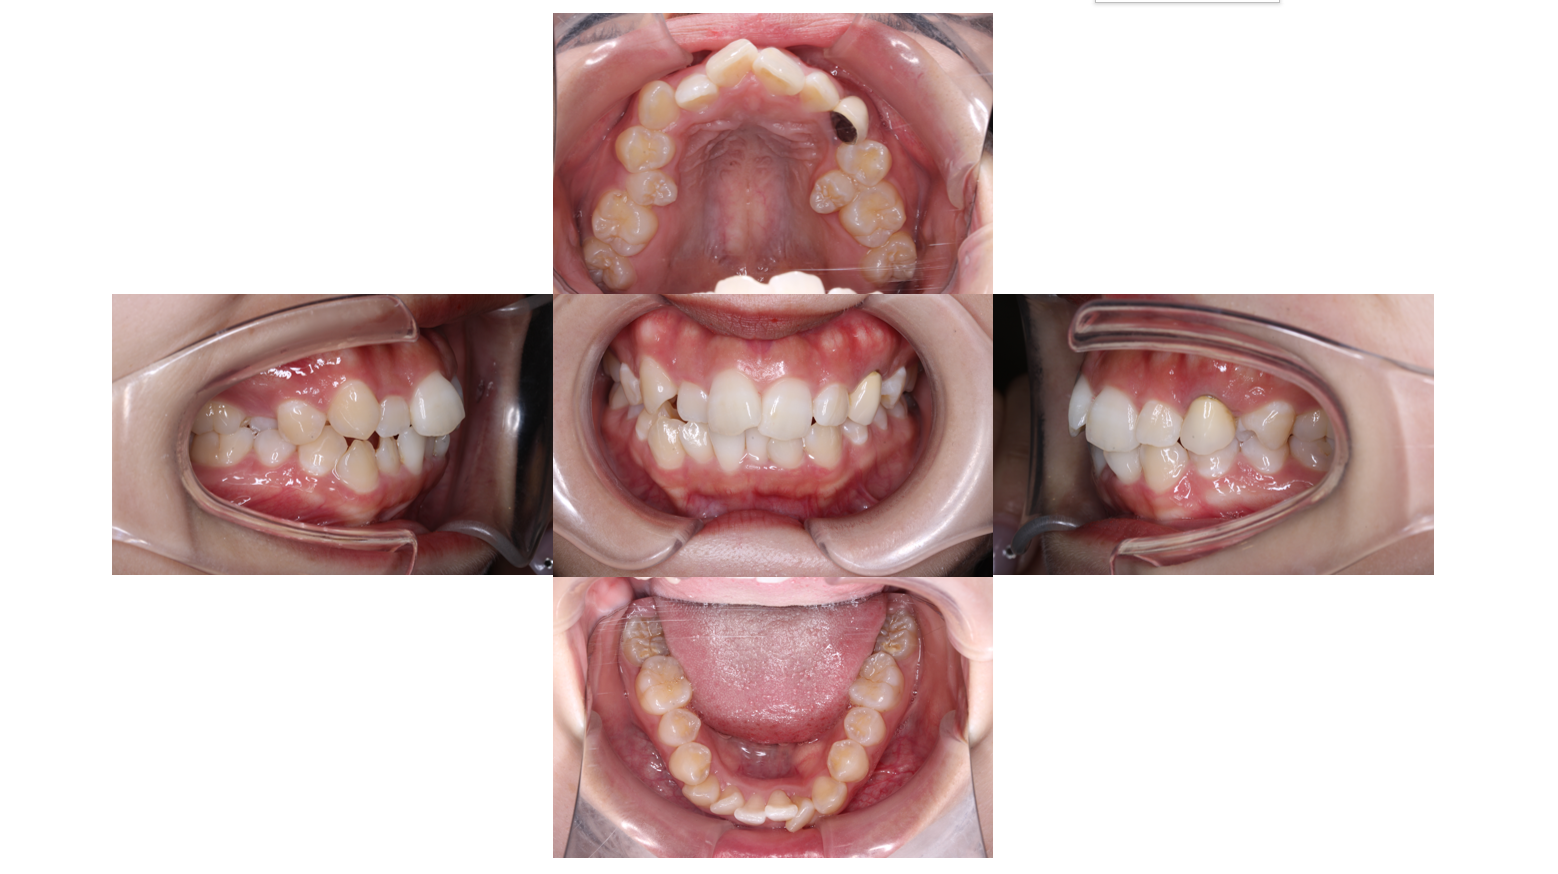

Before

主訴 | 【主訴】歯の凸凹を治したい 【診断・症状】上下凸凹 |

抜歯 | 有(上5,5)(下5,5) |

矯正の装置 | 裏側矯正(舌側矯正) |